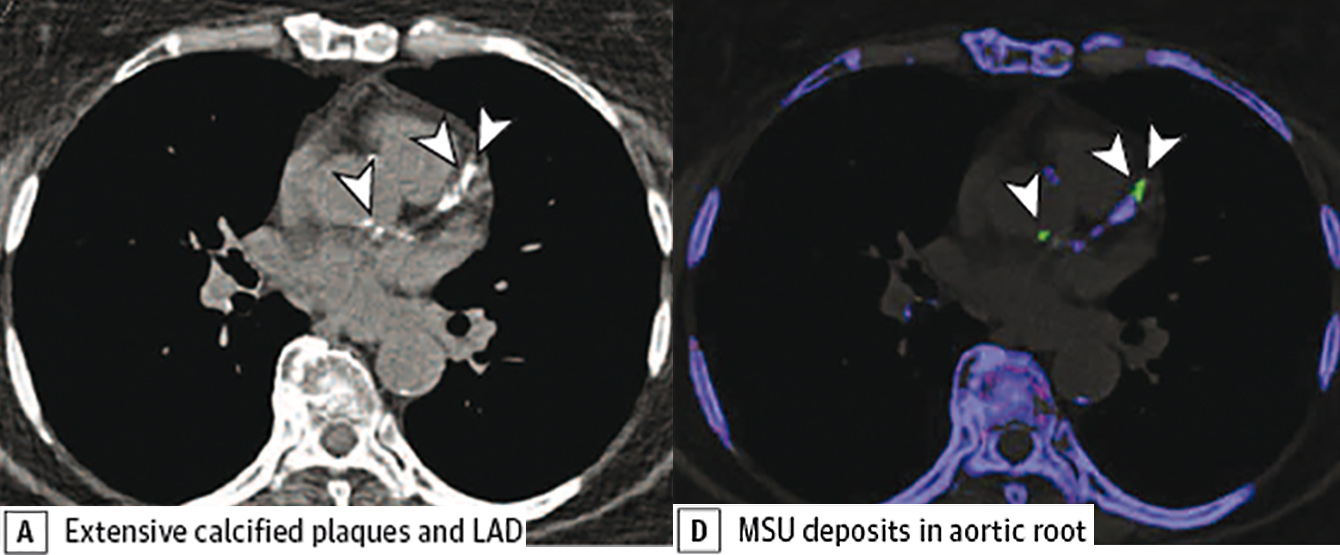

Im Bild: A natives CT zeigt deutliche Verkalkungen in der linken Koronararterie (weiße Pfeile), die sich violett in der DECT darstellen. Die grünen Ablagerungen entsprechen Uratablagerungen, die zwischengelagert sind. (Foto: Klauser/Univ.-Klinik f. Radiologie)

Das Auftreten von Gichterkrankungen nimmt in den letzten Dekaden zu. Verschiedene Studien haben bereits länger gezeigt, dass die Gicht als Risikofaktor für eine koronare Herzkrankheit im Zusammenhang steht. Bis dato war der Nachweis von Gichtkristallen in Geweben nur mittels Biopsie/Punktion und aufwändigen mikroskopischen Verfahren möglich. Die Arbeitsgruppe von Andrea Klauser von der Universitätsklinik für Radiologie (Direktor Werner Jaschke) erforscht bereits seit Jahren erfolgreich Gichtausfällungen in Gelenken mittels der Dual-energy-Computertomografie (DECT). „Für uns war es somit naheliegend, den Stellenwert dieser Bildgebungstechnik auch in der kardiovaskulären Bildgebung zu prüfen“, sagt Klauser. Für die Darstellung wird eine CT-Untersuchung mit zwei verschiedenen Strahlungsenergien durchgeführt. „Es wird ein CT-Gerät eingesetzt, das Zweienergiemessungen ohne relevante Erhöhung der Strahlendosis mit höchster Auflösung ermöglicht“, so die Radiologin. Das Hauptziel dieser ersten, kürzlich im JAMA Cardiology publizierten Studie, war die Prüfung der Möglichkeit von DECT im Nachweis von kardiovaskulären Harnsäureablagerungen (Uratablagerungen). „Dafür wurden DECT-Untersuchungen von Patienten mit Gicht und ohne Gicht prospekiv untersucht und die Untersuchungsergebnisse verglichen“, beschreibt Andrea Klauser die Vorgehensweise. Insgesamt wurden 59 GichtpatientInnen (mittleres Alter 59) und 47 Kontrollen (mittleres Alter 70) untersucht.

Die Studie wurde in enger Zusammenarbeit mit der Universitätsklinik für Innere Medizin II (Direktor Günter Weiss) im Zeitraum von Jänner 2017 bis November 2018 durchgeführt. „Der Calcium Score der Koronargefäße, also der quantitativer Nachweis von Kalkablagerungen mittels CT, ist ein gut etablierter Marker für die Einschätzung des Risikos, an einer koronaren Herzerkrankung zu erkranken“, weiß Klauser. Deshalb wurde mittels CT simultan der Calcium score und die Uratablagerungen in den Koronorien und der Aorta gemessen. Darüber hinaus wurden in Kooperation mit dem Department für Anatomie, Histologie und Embryologie (Direktorin Helga Fritsch) DECT positive Proben von Uratablagerungen in Gefäßen mittels Polarsiationsmikroskop korreliert. Es wurde die neue Methode mit einem etablierten Verfahren (Biopsie) verglichen, um dadurch diagnostische Fehler auszuschließen.

„Zusammenfassend kann gesagt werden, dass in der Studie erstmalig gezeigt werden konnte, dass DECT die Erkennung vaskulärer Uratablagerungen ermöglicht, die signifikant häufiger in GichtpatientInnen gefunden wurden. Diese neue Technik, die nicht nur invasive Eingriffe erspart, benötigt auch keine Kontrastmittel. Sie könnte somit in Zukunft einen wichtigen Beitrag in der Diagnostik und dem Management von Gichtpatienten mit Risiko einer kardiovaskulärer Erkrankungen leisten“, ist Andrea Klauser überzeugt.